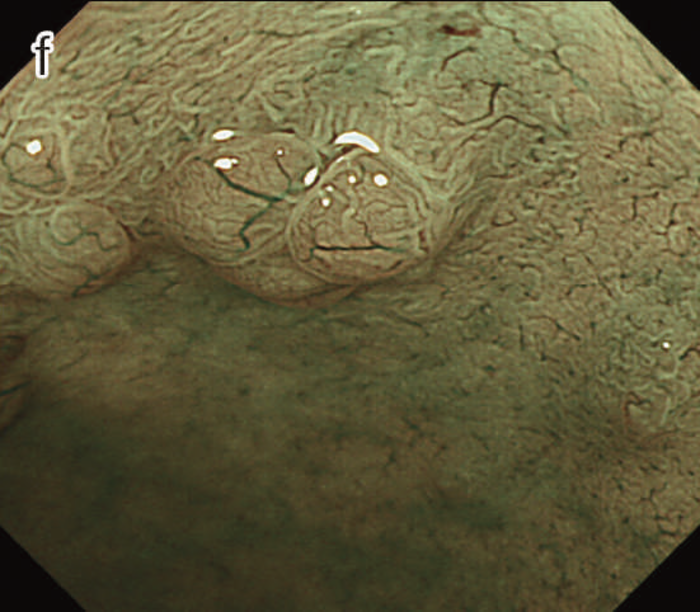

- NBI拡大像:口径不同,不均一な微小血管と不整な表面構造所見を認めた。

- pit pattern像:小型の類円形,管状pitを認めた。